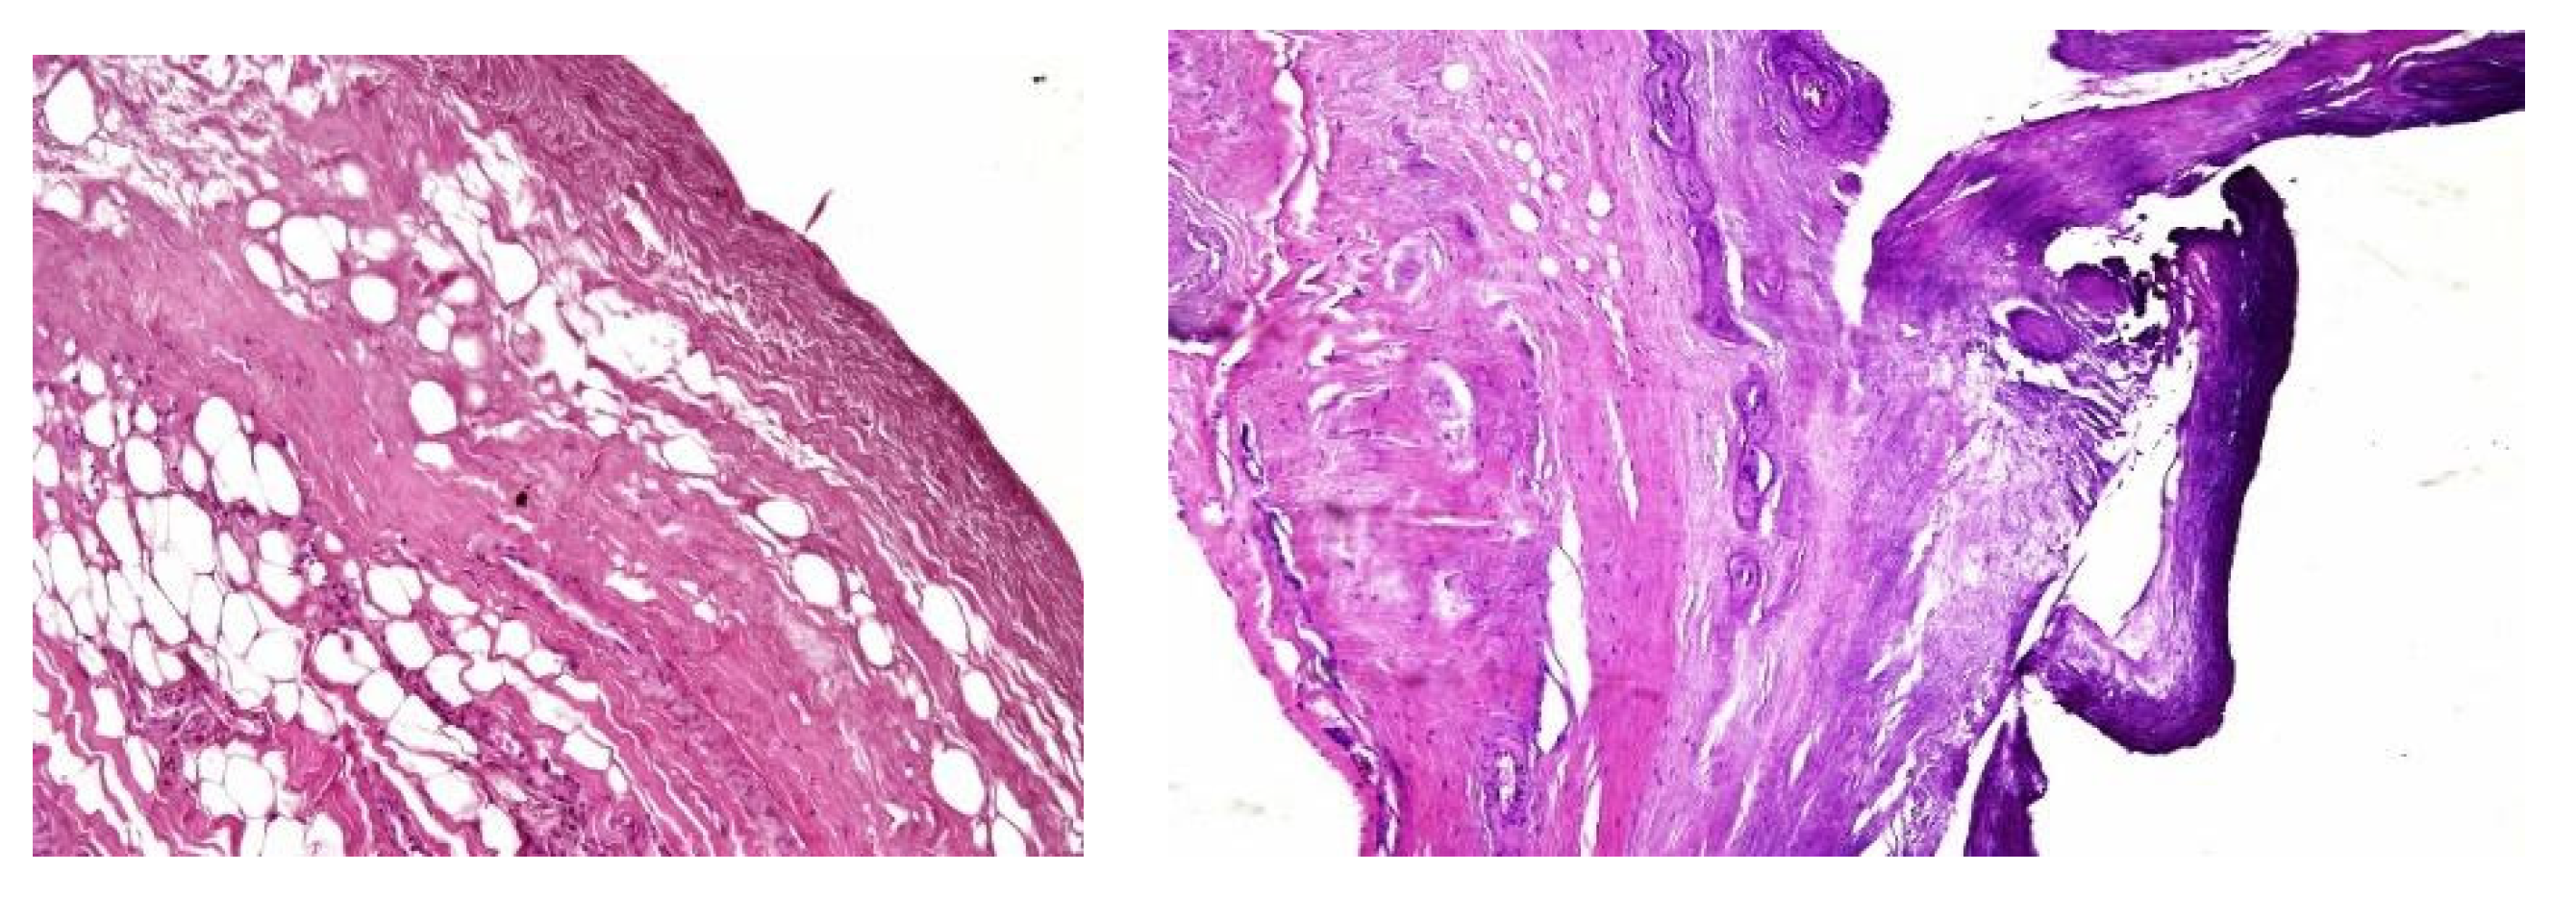

The second patient was a 44-year-old woman who had undergone PD for 11 years. The patient was referred for nausea, vomiting and metrorrhagia accompanied by a palpable mass in the lower abdomen. A CT scan revealed the presence of an abdominopelvic tumor measuring 12-cm in diameter, suggestive of a uterine fibroid causing compression of the rectum. A hemostatic curettage was performed in an attempt to postpone surgery, which proved unsuccessful. Then, laparotomy and a definitive transfer to hemodialysis treatment was decided. The intraoperative macroscopic appearance of the parietal and visceral peritoneum revealed only some areas of peritoneal fibrosis, except for the pelvic peritoneum which showed extensive fibrosis (Image 2). The fibromatous uterus was encapsulated in a pelvic “cocoon” and the rectosigmoid junction adhered to this “pelvic block”.

Image 2. Intraoperative finding – thickened peritoneum, ascites.